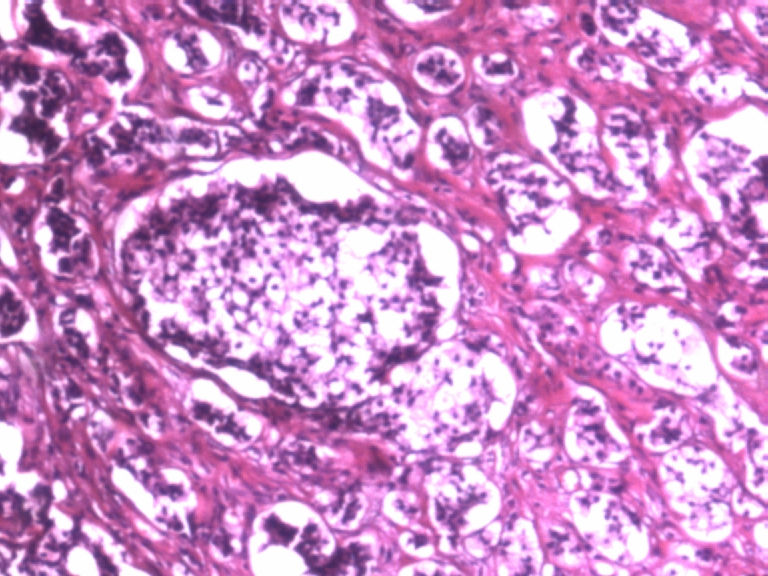

男,50岁,阑尾长7厘米,直径0.4---0.6厘米。剖开:尖端看见淡黄色区,不规则,界限欠清,0.15*0.2厘米,质中。

×参考诊断

考虑阑尾类癌

像类癌,有些粘液,标记一下Syn、CgA,有可能是杯状细胞类癌

按照胃肠胰腺神经内分泌肿瘤WHO2010分类,该例应属于NET G1(神经内分泌瘤,1级)。需标记Syn, CgA, Ki67.

倾向神经内分泌肿瘤,建议做CgA、SYN、Ki-67检查。